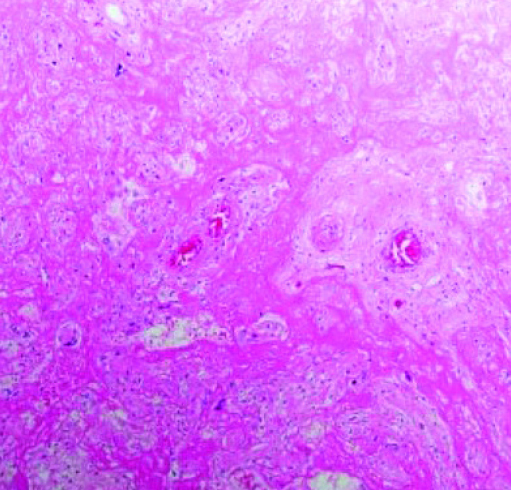

Массивное выпадение фибрина (см. рис. 3) — очень заметный и яркий признак. Иногда ворсины настолько замурованы выпавшим фибрином, что их трудно найти и рассмотреть, циркуляция материнской крови нарушена. Газообмен в плаценте значительно снижается или вовсе прекращается, что ведет к гипоксии и гибели плода.

Тромбоз межворсинчатого пространства (см. рис. 4). В сосудах формируются слоистые тромбы, оттесняя на периферию ворсины, которые перестают участвовать в газообмене.

Иван Сахаров обратил внимание, что изменения настолько яркие, что видны на макроскопическом уровне. Если в норме плацентарная ткань рыхлая, насыщенного красного цвета и напоминает пропитанную кровью губку, то при тромбозе становится желтовато-серой, очень плотной и сухой. В ней имеются заполненные кровью участки — это кровоизлияния и формирующиеся тромбы.

Сканируя гистологические препараты на малом увеличении, мы видели крупные участки тромбоза с массивным выпадением фибрина в межворсинчатом пространстве. На большом увеличении в периферии участков тромбоза наблюдается воспалительная инфильтрация в ворсинах и межворсинчатом пространстве. Можно рассмотреть, как фибрин буквально заклеивает собой ворсины.

В основном это свежий фибрин, хотя наблюдаются и участки более зрелого фибрина. То есть на морфологическом уровне мы предполагаем, что поражение плаценты происходит достаточно быстро и ведет к гибели плода. Все это подтверждается и клиническими данными.